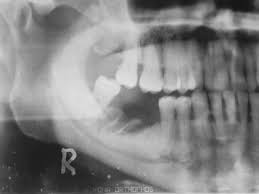

En un entorno de la vida real, nuestros datos confirman que la osteonecrosis de la mandíbula relacionada con bifosfonatos, asociada al zoledronato en la osteoporosis es inusual, aunque ligeramente más común en comparación con los bifosfonatos orales. También creamos conciencia sobre las pautas de cuidado dental y una mayor vigilancia al usar bifosfonatos en pacientes con exposición previa a denosumab. Joint Bone Spine, 2 de junio de 2023